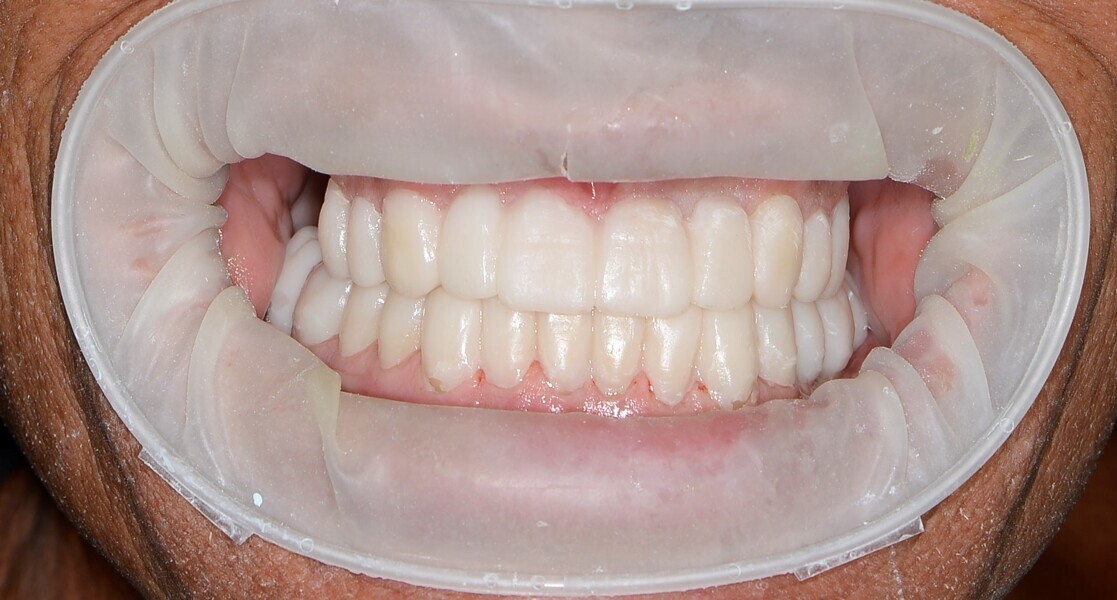

During the first visit, we checked the centric relation with cotton rolls, eliminating the posterior mesialising precontact and then performed a direct composite aesthetic and functional mock-up in this new position, not only to motivate the patient regarding the final result but also to help him understand better overall why tongue therapy, tooth alignment and dental resurfacing for augmentation of the vertical dimension of occlusion were required (Figs. 14 & 15).

After the first phase of aligner treatment, we had achieved better inter-arch coherence, better maxillary arch expansion, and some space for improving the anterior tooth proportions restoratively (Fig. 19). We then temporarily restored the anterior teeth directly with composite, closing the spaces, improving the tooth proportions and further increasing the maxillary arch expansion (Fig. 20). We used restorative arch expansion to reduce the orthodontic destabilisation of the teeth to achieve the correct inter-arch coherence and retain the teeth in the cortical bone.38 A refinement aligner phase was undertaken to improve the final alignment of the gingival zenith and to improve the inter-arch coherence (Fig. 21). The periods of the first orthodontic phase and of the refinement were used to augment the mandibular and maxillary bone and to place the implants (Fig. 22). At the end of the orthodontic treatment, the case was finalised with ceramic veneers in the anterior area and temporary restorations on the implants in the posterior area (Figs. 23–26).